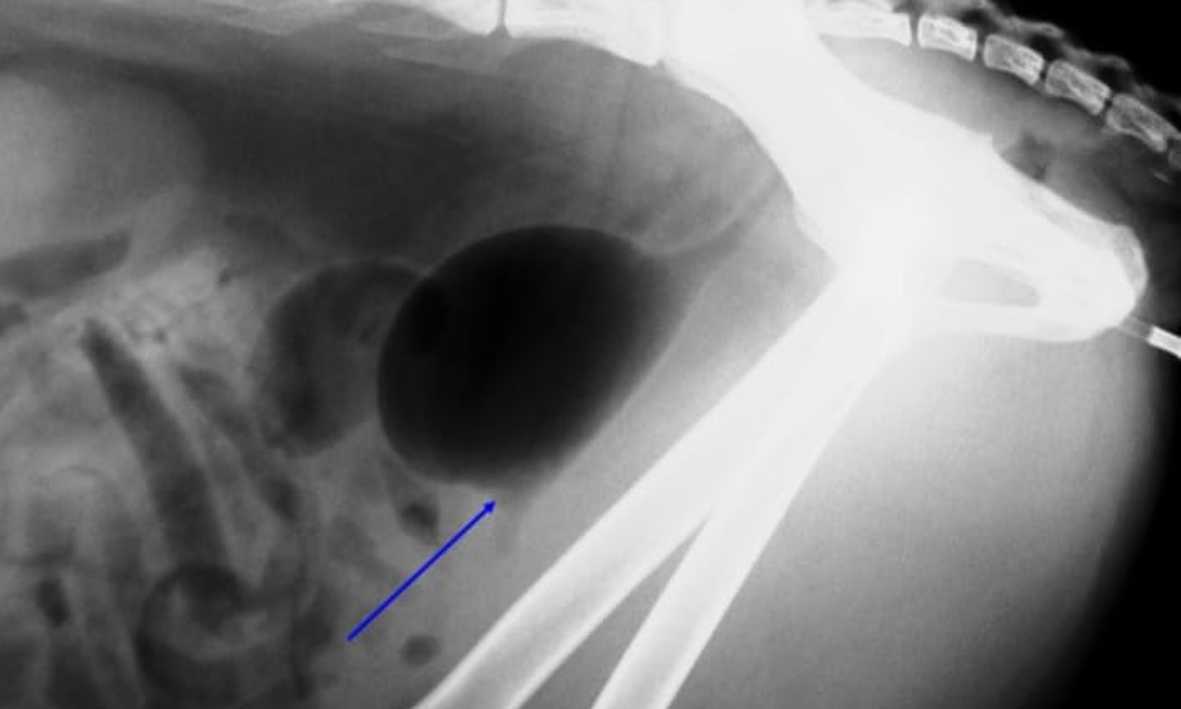

Diagnóstico por Imágenes

Radiografías Digitales, de contraste y simples, mielografías, ecografías.